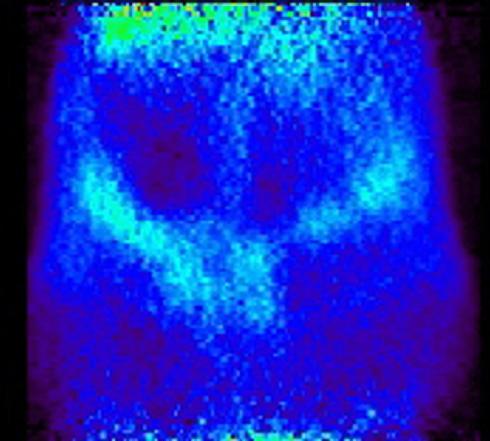

Just as it is possible to label a drug to find out whether it crosses the blood-brain barrier and then to measure the uptake and washout kinetics into the brain, it is also possible to use the labeled drug to measure uptake elsewhere. In this case the question is whether a drug reaches a fetus across the placental barrier. Reasons can include a desire to treat the fetus, or a desire to choose a drug partly on the basis of its exclusion from the fetus to minimize fetal toxicity and teratogenicity. These examples show selected images obtained from a study of live pregnant rats injected with I-124 labeled drug at 8, 11, 12 and 20 days of gestation. Injections were done at varying times, images shown are primarily of the abdomen only.

The “string of pearls” image of the fetuses is visible in the images. The rats had at least nine fetuses. From the whole-animal image at 8 days it is clear that this molecule did NOT accumulate well in the uterus or fetuses. The vast majority of administered dose was excreted. This can be a good result, of course. Further, uptake in this case appears to be in the placental areas and not in the uterine wall or contained within the fetuses.